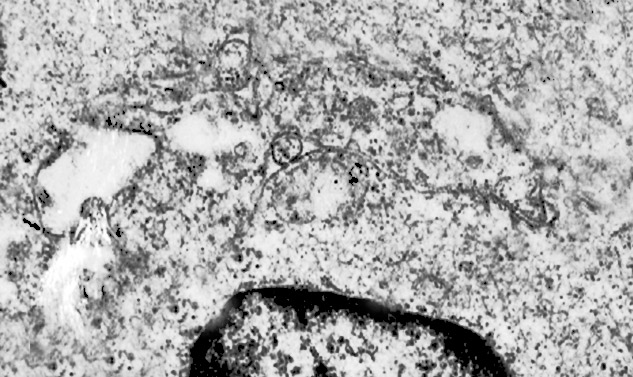

2/a AUTOFAGOSOMA

I focolai di macroautofagia possono essere presenti in zone diverse del citoplasma. La loro microstruttura di base è costituita da una area vacuolare demarcata da una membrana a doppio strato; l’area cava è occupata per quote variabili da materiale amorfo,da aggregati filamentosi,da frammenti di organuli,da gruppi granulosi, il tutto in diversi stati di conservazione. Questi focolai macroautofagici appaiono come strutture avulse dalle mutevoli condizioni bio-morfologiche del citoplasma nel quale si sono formate. E’ frequente il riscontro di cellule di aspetto cribroso per la esistenza di micro vacuoli scavati nel citosol e per la dilatazione delle cisterne del reticolo endoplasmico contengano nel citosol una formazione macroautofagica occupata in parte da materiale amorfo e filamentoso.

Non mancano elementi cellulari,forniti di un citosol contenente solo ribosomi liberi, rare strutture reticolo endoplasmatiche in via di disgregazione e molto materiale amorfo, essere occupati da un focolaio di macroautofagia con aggregati di filamenti.